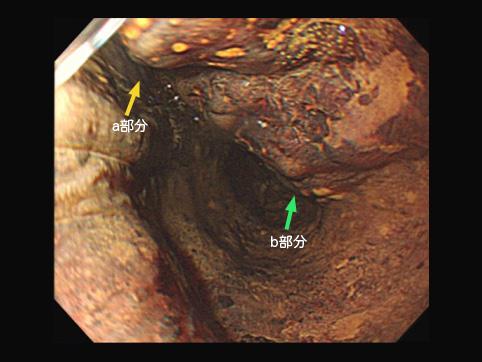

疾患(病理主体)の分類悪性上皮性腫瘍/扁平上皮癌

部位(臓器別)食道/中

検査方法内視鏡

病変の最大径(ミリ)20〜24

腫瘍の深達度sm